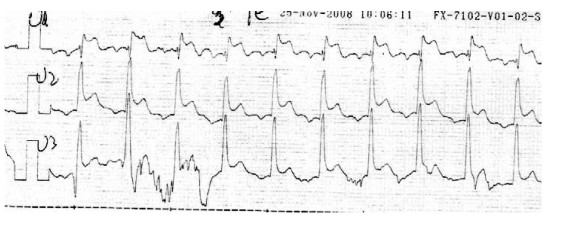

En el postesfuerzo inmediato se comienza a observar elevación del ST en V1 a V3 que alcanza los 2,5 mm, en este momento se administra nitritos sublinguales disminuyendo progresivamente la sintomatología, los cambios electrocardiográficos persisten hasta los 6 minutos del postesfuerzo (figuras 3 y 4).

Figura 4. Postesfuerzo 3 minutos